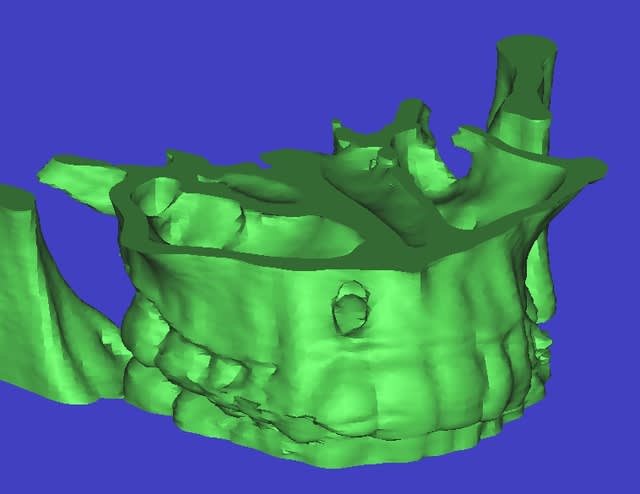

pano....youpie...scan...et là je crois qu'on décroche le ponpon...

super sinus...bien sûr la dent est condamnée...mais vous feriez quoi pour avoir une chance de planter dans quelques mois...ou du moins éviter un "énorme" défaut osseux qui sera difficilement gérable d'un point de vue esthétique...???

t'as vu la taille du kyste??? il va jusqu'au sinus et se prolonge derrière la 11...la 12 ne tiens que par son ligament palatin...

pour D57...voussure vestibulaire...je sais pas trop s'il reste une corticale...ou si oui ultrafine...

le risque...perforation du sinus si la membrane kystique y adhère fortement...

je pensais tenter une sorte de ROG...en tapissant le fond (vers le sinus) avec une membrane collagène, et une autre vestibulaire au cas où il n'y ait plus d'os...

la question est plutôt...que mettre entre...

rien, des éponges hémostatiques, du biomat (lequel???biooss??) voir une membrane titane pour bien maintenir le volume???